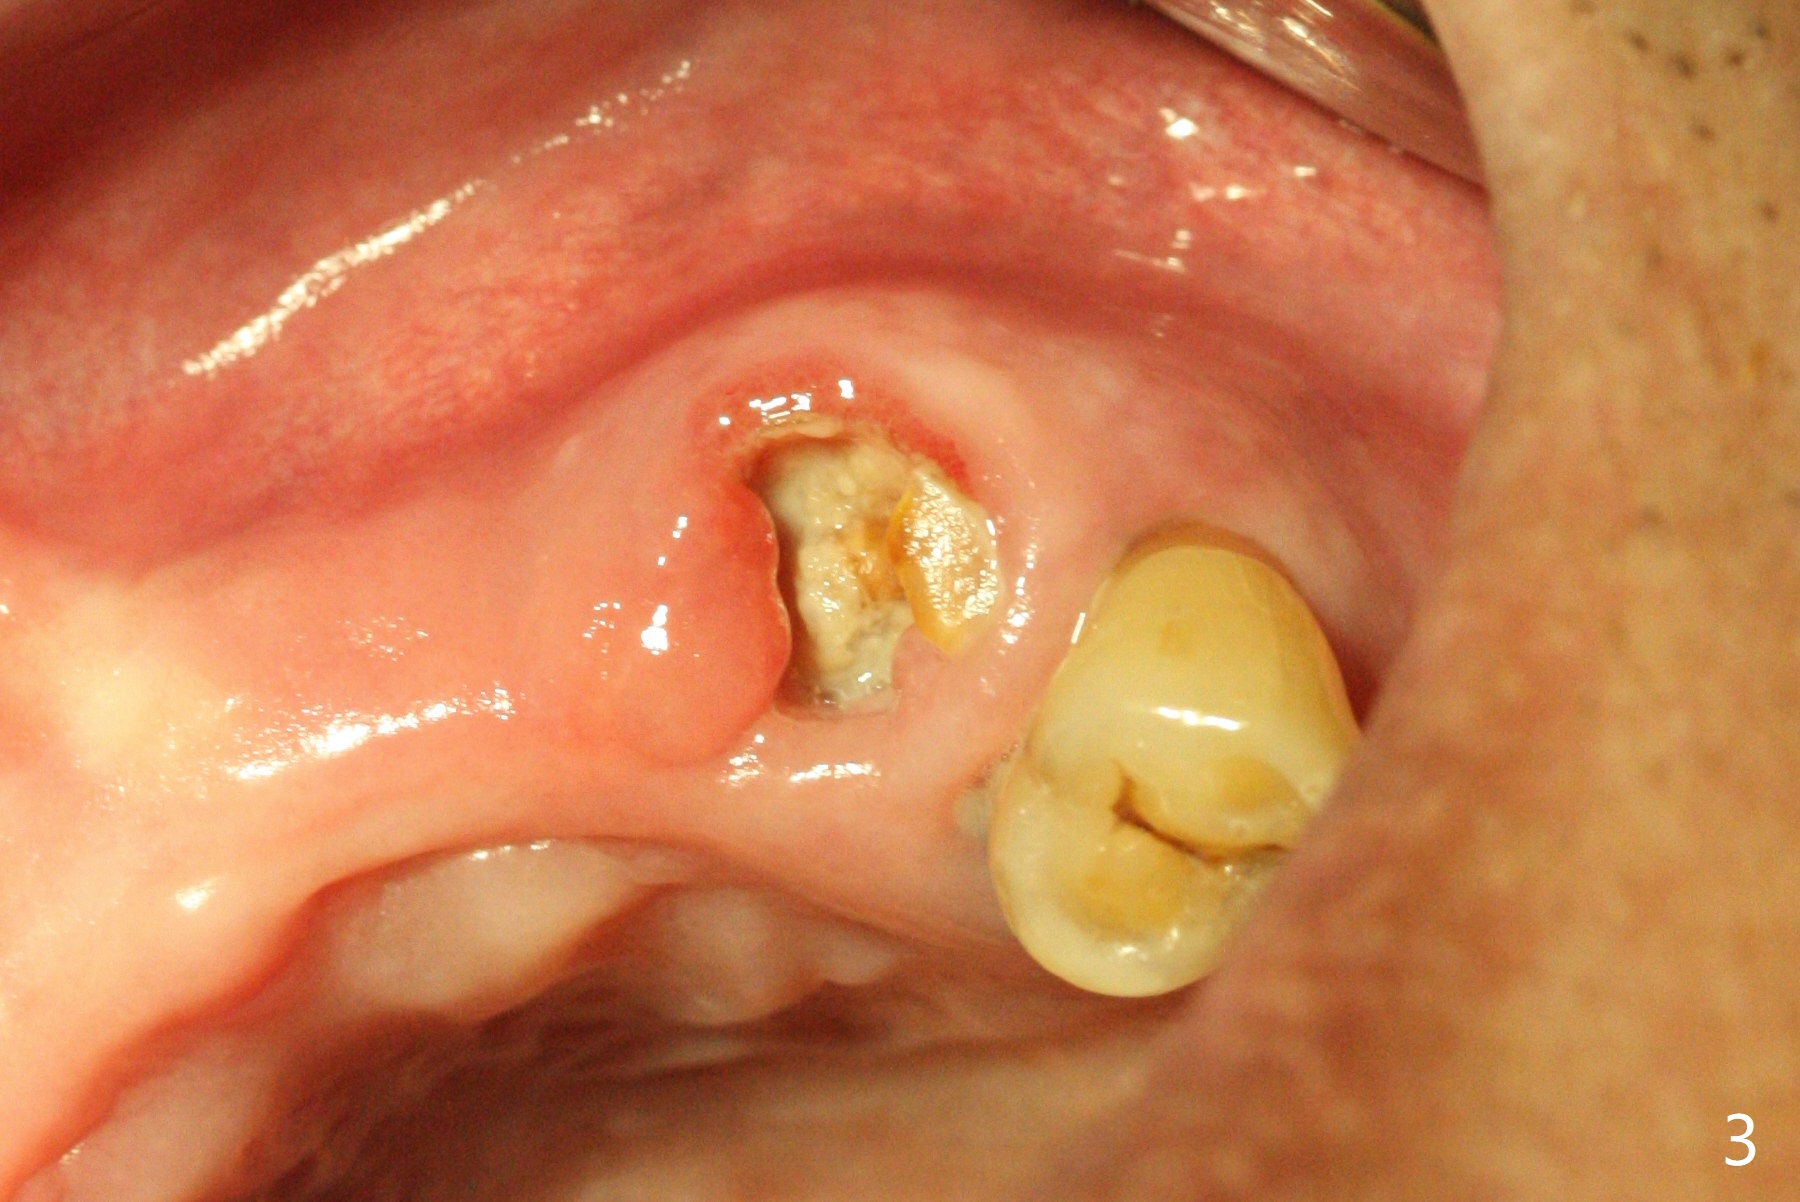

A 81-year-old man with upper and lower RPDs (Fig.1) requests extraction of the tooth #11 (Fig.2,3). After discussion, he agrees with socket preservation using Osteogen plug (Fig.4 O). The density at #11 is in fact higher than the neighboring healed socket (#10). Due to failure to transfer the flap to cover the socket and poor oral hygiene, the wound does not heal as well as expected 13 days postop (Fig.5).